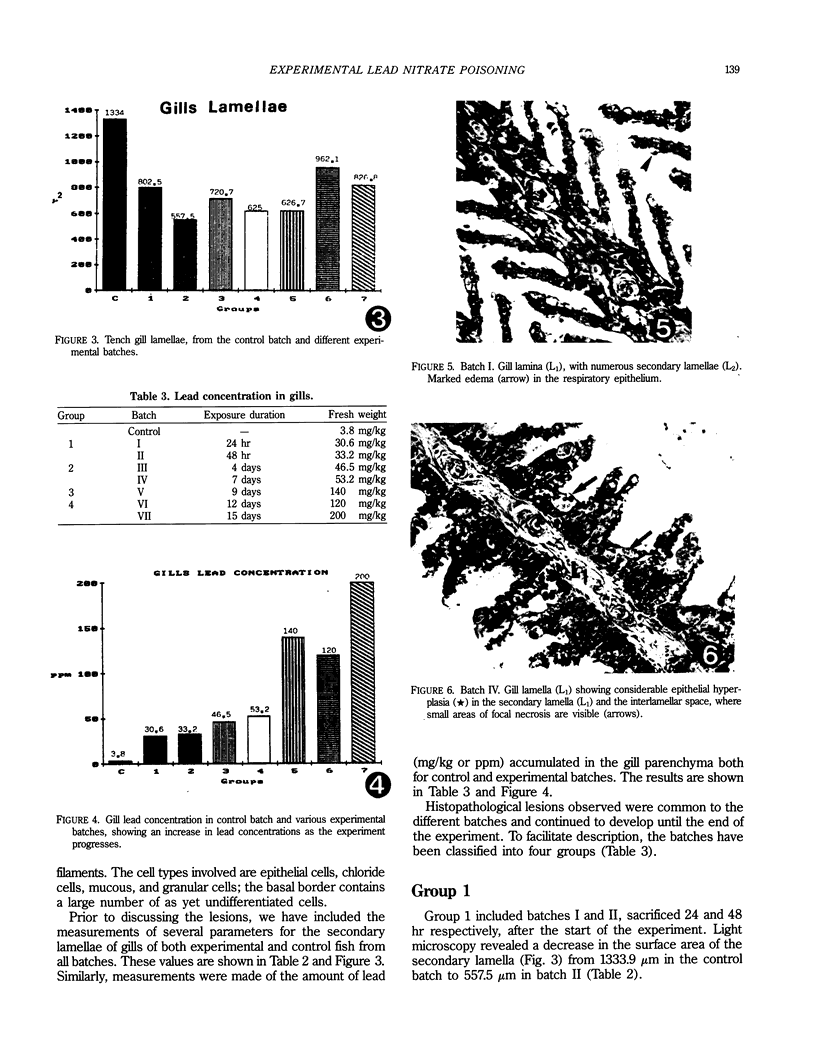

A microscopic, ultrastructural, and morphometric study was made of the gills of tench (Tinca tinca, L.) subjected to acute experimental lead nitrate poisoning. Twenty-one adult tench were subjected to poisoning and a further 22 were used as controls. Lesions were characterized by the appearance of edema and epithelial hyperplasia and necrosis, both in cells forming part of the filtration barrier and in those in the interlamellar space. These processes developed in the course of the experiment, leading to the death of tench after 12 to 15 days of exposure to 75 ppm lead nitrate, at which point the concentrations of lead in the gills had reached their maximum.